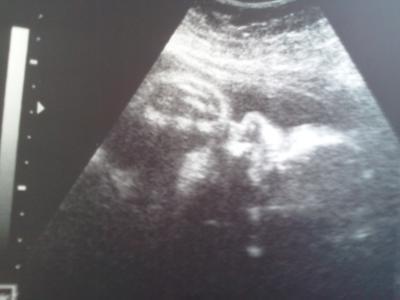

Dem Söhnchen geht es gut. Auf 2600g hat sie ihn geschätzt=D Nun geht sie auf die letzten Tage noch in den Urlaub... PRIMA=!!! Die vertretung is ja der knaller *_* Strepto. Test war leider positiv aber was solls... Schönes Foto beim Nuckeln gab es =D

Bild zu War grad bei meiner FÄ .. - Forum für Juli - Mamis